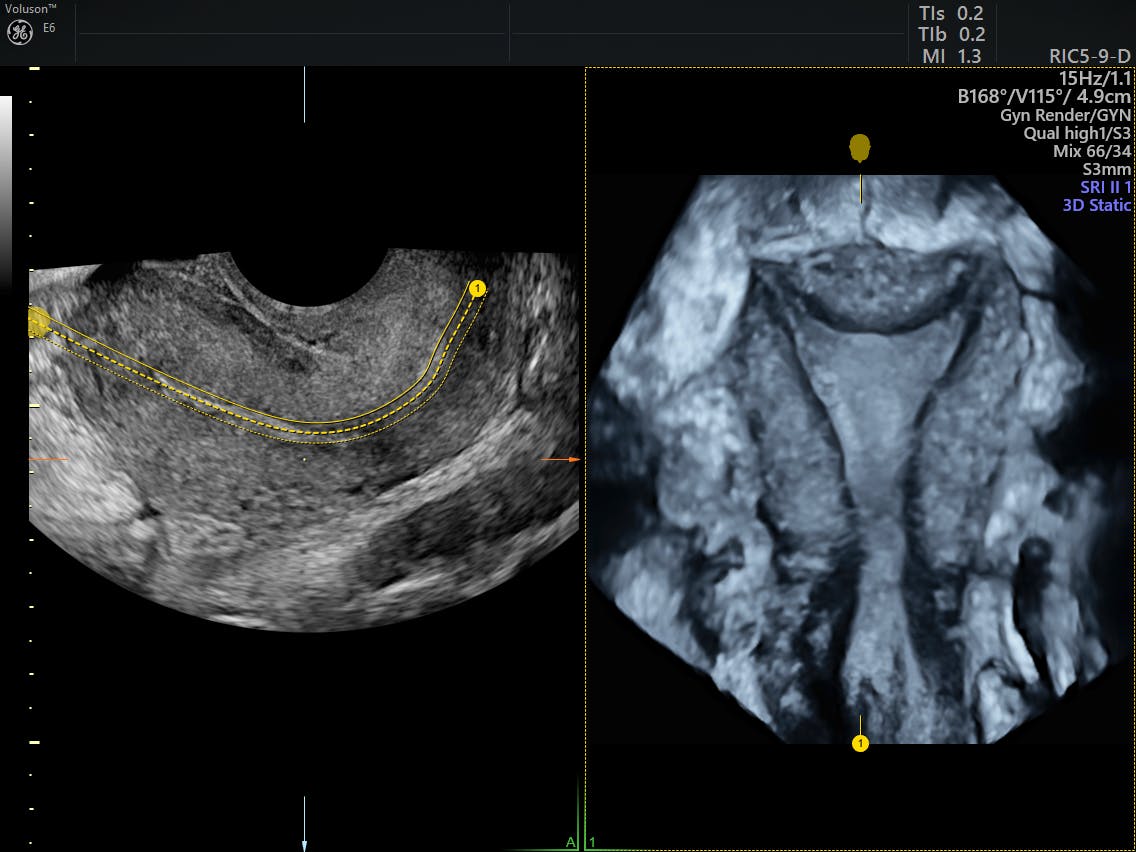

Noninvasive ultrasound diagnosis of endometriosis Does Endometriosis Go Away After Uterus Removal Endometriosis may return after a hysterectomy, even after removal of the ovaries, and people may need further. Endometriosis can and often does come back after surgery, especially if the surgeon did not remove all of the endometrial tissue. Surgery is also an option if endometriosis is. This article will discuss surgical options for endometriosis, what endometriosis recurrence means, why endometriosis. Does Endometriosis Go Away After Uterus Removal.